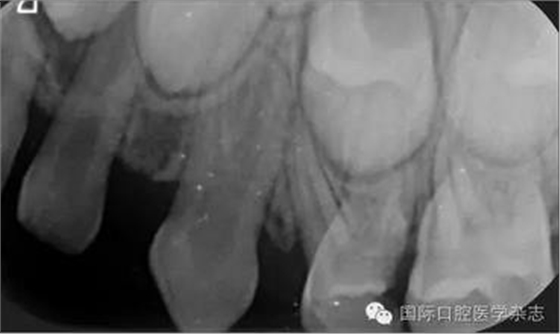

根尖X線片檢查偶然發(fā)現(xiàn):左側(cè)上頜乳尖牙呈雙根,髓腔寬大,牙根自接近根中1/3起至根尖分為明顯的近中及遠(yuǎn)中2個牙根(圖2)?;純杭议L知情同意后,拍攝其他3張乳尖牙根尖片,以觀察牙根是否有異常。X線片示:右側(cè)上頜乳尖牙呈雙根,且形態(tài)、大小及根分叉位置與左側(cè)相似(圖3)。雙側(cè)下頜乳尖牙的形態(tài)及牙根未見異常。詢問病史了解到,患兒體健,足月順產(chǎn),其母妊娠期間無感染或服藥史,患兒嬰幼兒期無外傷史,無兄弟姐妹。

圖2左側(cè)上頜乳尖牙X線片

Fig 2 Maxillary leftprimary canine radiograph

圖3右側(cè)上頜乳尖牙X線片

Fig 3 Maxillary right primary canine radiograph